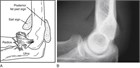

Radial head fractures, generally occurring after a fall onto an outstretched hand, present with pain at the elbow and limited range of motion with extension, pronation, and supination. They can be subtle or radioccult on plain films, but the presence of a "sail sign" can alert the clinician that a fracture is present. For nondisplaced or minimally displaced fractures, treatment includes over-the-counter analgesics, sling for comfort, and early mobilization. Displaced fractures may require orthopedic intervention.